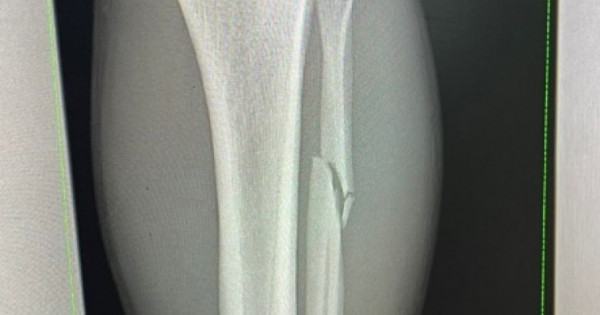

«Shaıqastyń birinshi mınýtynda aıaǵymdy syndyryp aldym. Segiz buryshqa munan da kúshti bolyp oralamyn», dep jazdy qazaq oǵlany óziniń ınstagramdaǵy akkaýntynda.